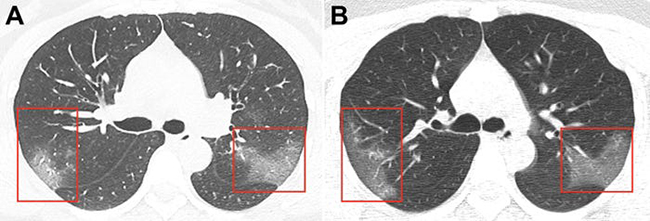

Đây là hình ảnh chụp CT phổi của một phụ nữ 33 tuổi ở bệnh viện Lan Châu, Trung Quốc. Cô nhập viện trong tình trạng sốt và ho trong 5 ngày, bác sĩ phát hiện số lượng bạch cầu của cô thấp và có dấu hiệu nhiễm trùng phổi. Bản quét CT cho thấy có các mảng trắng giống như thủy tinh bị mờ nằm ở thùy phải, sau đỉnh thùy trái.

Paras Lakhani, một bác sĩ X-quang tại Đại học Thomas Jefferson, người không tham gia vào nghiên cứu nhưng kiểm tra các hình ảnh, nói với trang Business Insider. "Đây là chất lỏng trong không gian phổi". Các nhà nghiên cứu cũng thấy rằng các mảng trắng trên phổi của người phụ nữ rõ rệt hơn trong hình ảnh thứ 2, được chụp lại sau 3 ngày sau lần đầu tiên. (Ảnh: Business insider)